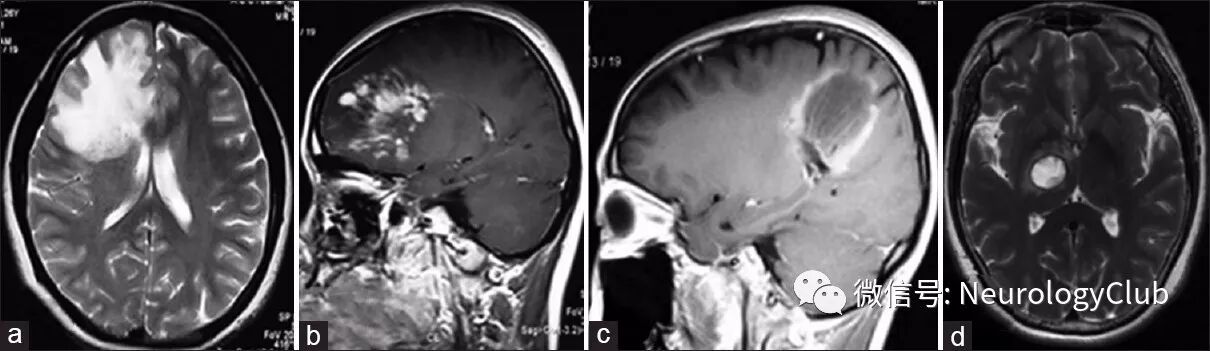

1. MRI平扫:TDLs病灶常为T1WI低信号,T2WI高信号,较CT显示的病灶范围大。约70-100%TDLs患者的病灶在T2WI上为高信号,边界清楚(图5b),而少数病灶的边缘可见T2WI低信号(图4a)。大多数TDLs病灶具有占位效应(图1a,2b,2c,和3a),但较脑肿瘤轻,病灶周围常可见水肿。在急性或亚急性期,水肿主要为细胞毒性水肿,DWI序列上为高信号(图4b)。经激素治疗后,病灶可在数周内变小或消失。

在中国,一项纳入60例TDLs患者的研究显示TDLs的病灶呈动态变化,和病情进展相一致:(a)在急性期(起病时间≤3周),病灶为斑片状或结节状强化(图5c);(b)在亚急性期(起病4-6周),病灶逐渐演变为开环、闭环或花环状强化,可伴有斑片状强化(图5d);(c)在慢性期(起病7周后),病灶仍呈开环或闭环强化,强化逐渐减弱或消失。

图4:T2WI上多发圆形的TDLs病灶,即“煎蛋”征(a);DWI序列示双侧侧脑室旁TDLs病灶呈高信号,伴有环形弥散受限(b);DWI序列可见PCNSL胼胝体压部病灶弥漫稍高信号(c);III级间变性星形胶质细胞瘤患者, DWI序列上可见右侧额叶片状低信号灶,周围可见弥漫高信号影(d)

图5:一例TDLs患者,增强T1WI可见闭环强化和开环强化,开口处朝向皮层;同时可见斑片状或结节状强化(a,起病22天);另一例TDLs患者,轴位T2WI可见双侧侧脑室额角和枕叶“云雾状”高信号灶伴随边缘低信号(b,起病30天);增强T1WI可见双侧侧脑室额角斑点状强化(c,起病10天);矢状位增强T1WI可见双侧侧脑室额角和枕叶“C”形强化,前者开口朝向侧脑室,后者朝向皮层(d,起病30天)